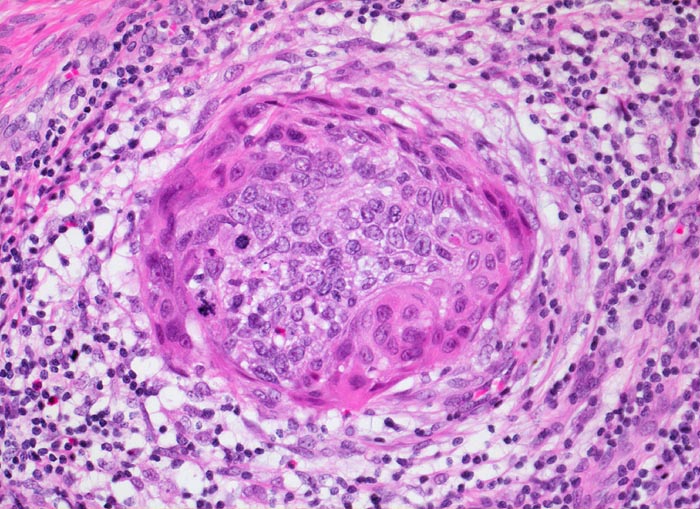

PathoPic ID 3461 - Mikroinvasives Plattenepithelkarzinom der Zervix

Mikroinvasives Plattenepithelkarzinom der Zervix

Invasiver Herd im Zervixstroma umgeben von desmoplastischer Stromareaktion und Entzündungsinfiltrat.

PAP V, HPV high risk Typen